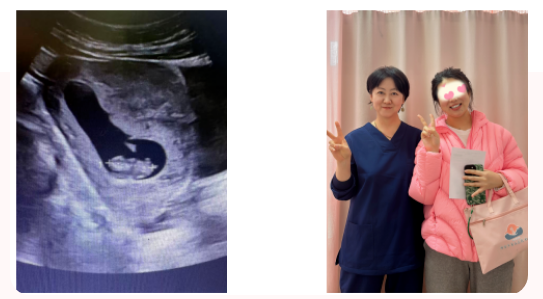

医患同心,其利断金。经过一段时间的精心调理与准备,好消息终于传来!该患者终于成功妊娠,并在妇产科团队的持续监测与守护下,目前已妊娠20周,B超显示胚胎发育良好,那颗历经风雨终于扎根的“种子”,正在这片被精心呵护过的“土地”上茁壮成长。